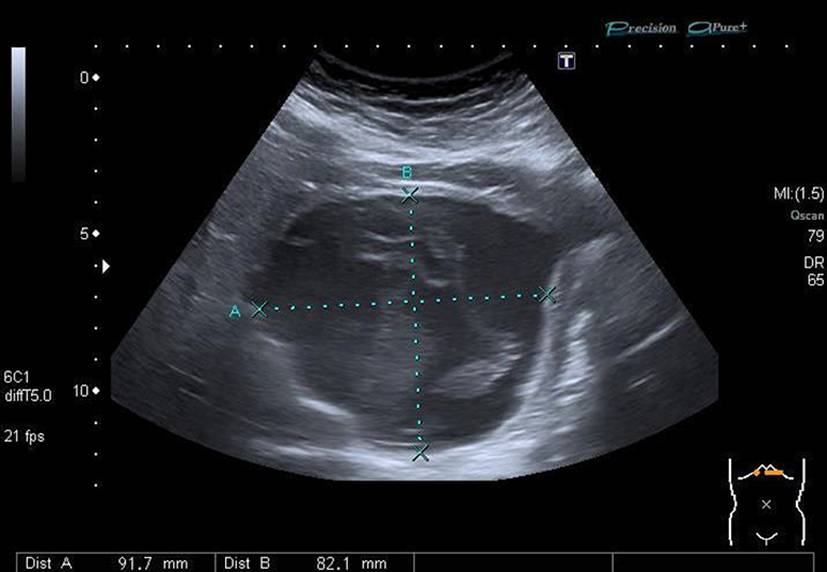

Die alveoläre Echinokokkose (AE) zeigt in der Bildgebung eine breite morphologische Variabilität und kann sowohl zystische als auch solide oder gemischt zystisch-solide Strukturen aufweisen (Abb. 1). Selbst für erfahrene Radiologen ist es oft schwierig, AE-Läsionen von malignen Erkrankungen wie intrahepatischem Cholangiokarzinom oder Lebermetastasen sowie von benignen Veränderungen wie Hämangiomen oder zystischer Echinokokkose zu unterscheiden. Zur Klassifizierung von AE-Läsionen wurden für Ultraschall, CT und MRT verschiedene deskriptive Systeme entwickelt [1315]. Diese haben aktuell vor allem in der Forschung eine Bedeutung. Im Ultraschall erscheint eine AE häufig als avaskulärer, gemischt echogener Tumor mit pseudozystischen oder verkalkten Anteilen, was gelegentlich Hämangiomen oder Metastasen ähneln kann [15]. Ein wichtiger Aspekt in der Bildgebung ist, dass der Nachweis von Verkalkungen nicht als Zeichen einer inaktiven Erkrankung gewertet werden darf [16].

Abb. 1

Verschiedene Präsentationen der alveolären Echinokokkose im Ultraschall. a AE, metastasenähnlich, b AE, hämangiomähnlich, c AE, primär zystisch, d AE, primär solide